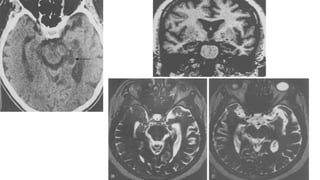

RADIOGRAPHIC FEATURES

MRI

MRI findings may be bilateral or unilateral and symmetric or asymmetric,

and include:

T2 hyperintensity

obasal ganglia (putamen and caudate)

othalamus ( hockey stick sign and pulvinar sign)

ocortex: most common early manifestation

owhite matter

persistent restricted diffusion on DWI (considered the most sensitive

sign)

Review of sequential studies also typically demonstrates rapidly

progressive cerebral atrophy.

hypometabolism on 18FDG-PET studies